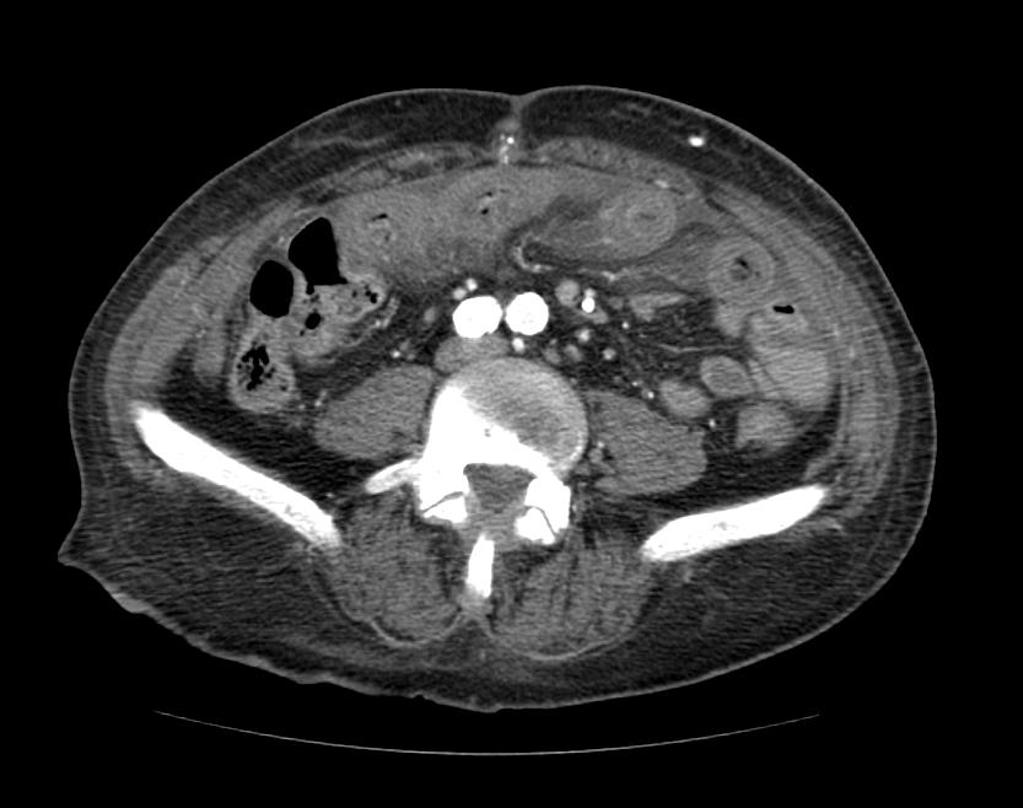

Ischémie mésentérique

Case courtesy of Radiopaedia.org. From the case Ischaemic bowel